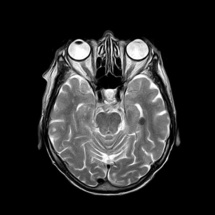

Imagen: toubibe. Fuente: Pixabay.

Usando la técnica de registro de imágenes con resonancia magnética (IRM) en bebés con hermanos mayores con autismo, un equipo de investigadores ha logrado predecir, con un 80% de acierto, qué bebés podrían desarrollar autismo a los dos años de edad.

En la presente investigación han participado cientos de niños de todo EEUU. En ella, Piven, junto a investigadores de diversos centros e instituciones de investigación estadounidenses, realizaron exploraciones de resonancia magnética a bebés a los seis, 12 y 24 meses de edad.

Descubrieron así que los bebés que más tarde desarrollaron autismo habían experimentado una hiperexpansión de la superficie de sus cerebros entre los seis y los 12 meses de edad, en comparación con los bebés que tenían un hermano mayor con autismo, pero que no mostraron evidencias de padecer el trastorno a los 24 meses o dos años.

Los científicos han relacionado ese aumento de la tasa de crecimiento de la superficie cerebral durante el primer año de vida de los niños con una mayor tasa de crecimiento del volumen cerebral total en su segundo año de vida. Además, establecieron que ese crecimiento excesivo del cerebro estaba relacionado con el surgimiento de déficits sociales autistas en el segundo año de vida de los pequeños.

Por último, los científicos tomaron los datos recopilados (resonancias magnéticas del volumen cerebral, área superficial, grosor cortical a los 6 y 12 meses de edad y sexo de los niños) y utilizaron un programa informático para clasificar a los bebés con mayor probabilidad de cumplir con los criterios para el autismo a los 24 meses.

De este modo, hallaron que las diferencias cerebrales a los 6 y 12 meses de edad en bebés con hermanos mayores con autismo predecían con bastante exactitud qué niños cumplirían con los criterios del austismo a los dos años. Previamente, se había detectado el autismo en niños analizando patrones dinámicos de la actividad cerebral con magnetoencefalografía (MEG), pero no en una etapa tan temprana.